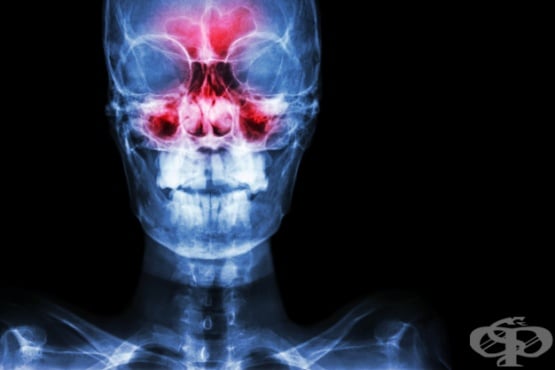

Синузит Възпалени синуси Синузит Симптоми при синузит Синузит Синузит Риноскопия Рентгенография максиларен синузит Компютърна томография етмоидакен синузит ЯМР синузит Одонтогенен синузит Лечение на синузит

СинузитВъзпалени синусиСинузитСимптоми при синузитСинузитСинузитРиноскопияРентгенография максиларен синузитКомпютърна томография етмоидакен синузитЯМР синузитОдонтогенен синузитЛечение на синузитЛечение на синузит

Синузитът, известен също като риносинузит, представлява възпаление на лигавицата, покриваща околоносните кухини (синусите). Възпалителният процес преминава най-често от носната лигавица към кухината на синуса и може да бъде с остър или хроничен (с периоди на затихване или обостряне на симптоматиката) характер.

Симптомите на синузит могат да включват: